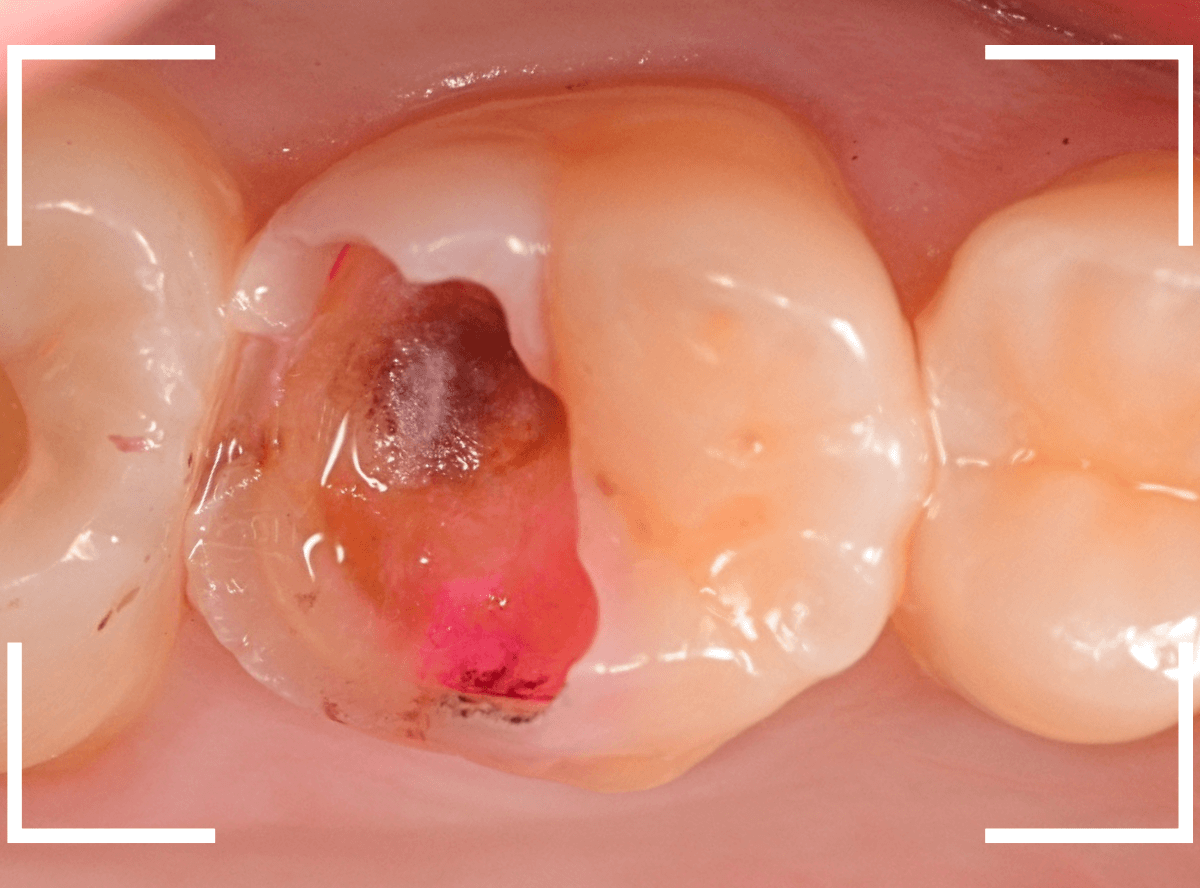

実際に使っている場面です。

神経に近い虫歯ですので、いつも以上に慎重に虫歯をある程度除去したところで、虫歯の状況を検知液で確認します。

薄く赤く染まっているところが虫歯です。

逆に、他の色がついているところは、虫歯ではないので、削らなくてもよいという事ですね。

全く染色されなくなりました。

これで全ての虫歯を除去したことになります。